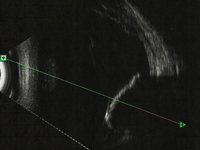

Las membranas fibrovasculares aparecen principalmente a lo largo de las arcadas vasculares y se visualizan como una estructura retiniana en forma de V (

Figura 9), porque el vítreo está parcialmente desprendido, en la cual el vértice de la V corresponde al punto de anclaje de las membranas.

Figura 9. Izquierda: membrana fibrovascular en V que provoca un desprendimiento de retina traccional. Derecha: desprendimiento de retina en “tienda de campaña”.

En caso de aumento de la tracción en estas membranas fibrovasculares puede producirse un desprendimiento de retina traccional, que se observa en la ecografía en forma de tienda de campaña (

Figura 9) o en sobremesa dependiendo de los puntos de tracción y de lo evolucionado que se encuentre. Estas adhesiones pueden producir un levantamiento del área macular.